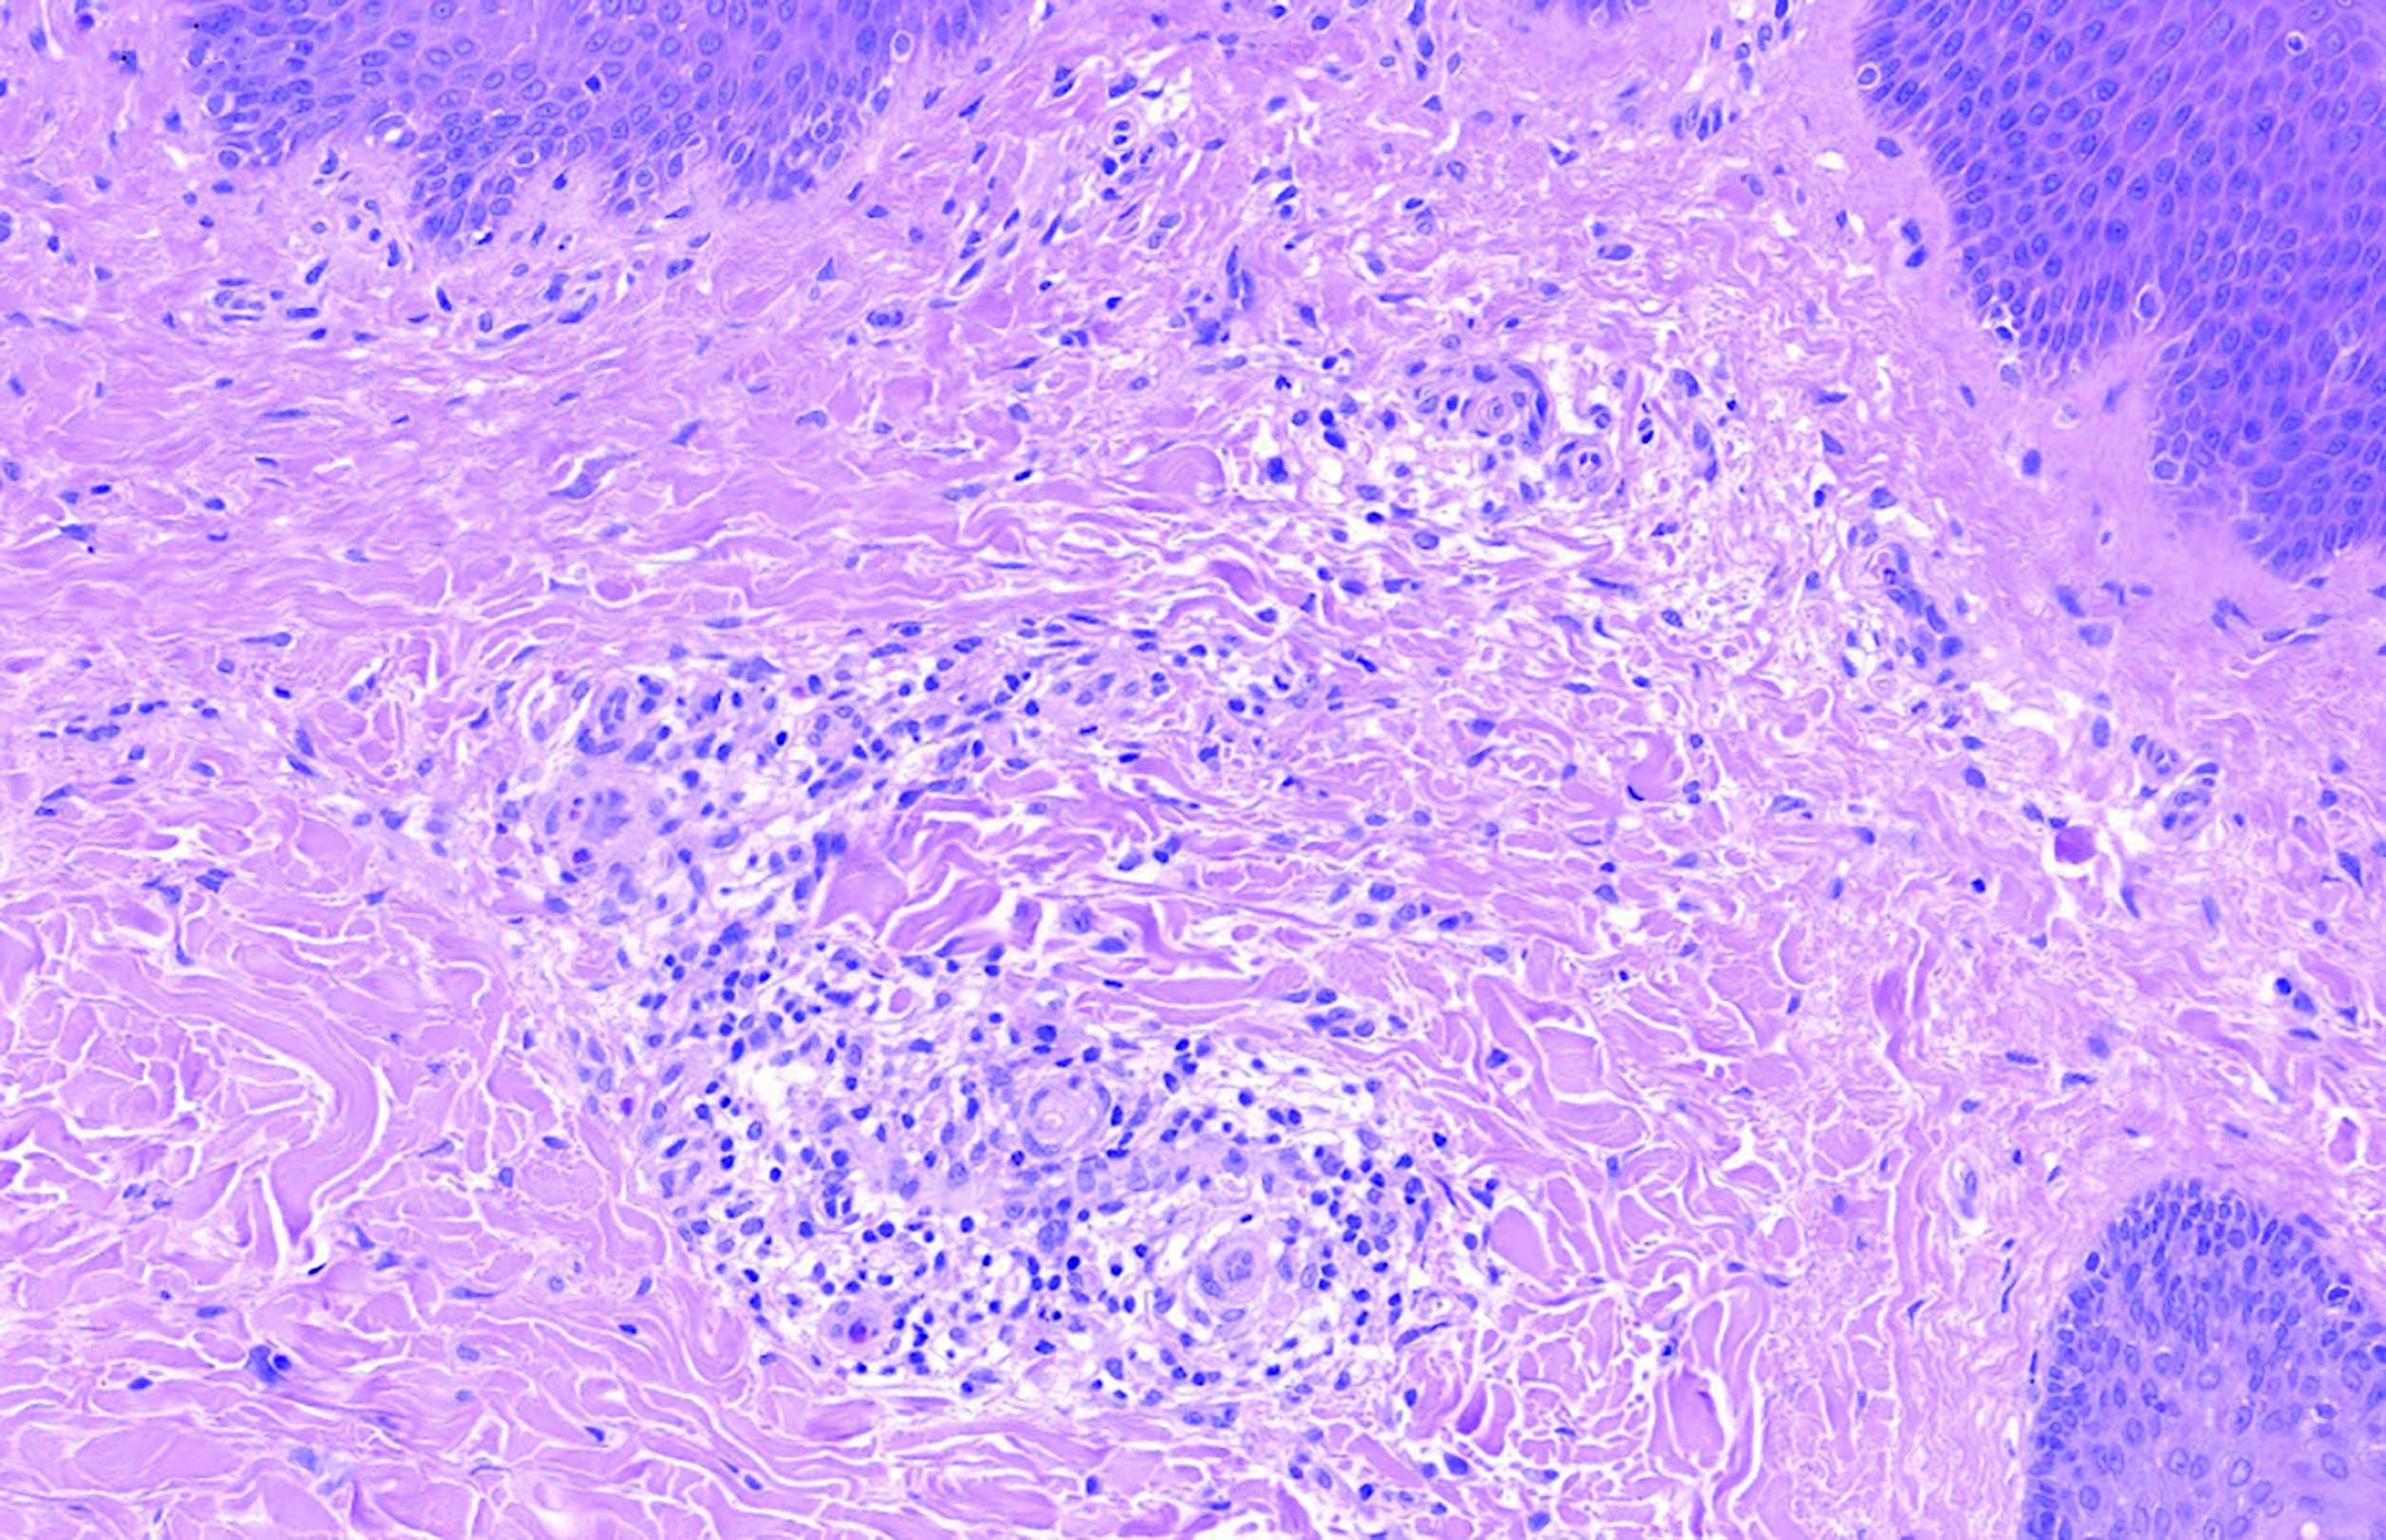

Для дифференциальной диагностики гистиоцитоза из клеток Лангерганса с другими гистиоцитарными опухолями было проведено повторное гистологическое и иммуногистохимическое исследование участка пораженной кожи. Гистологическое исследование показало, что в исследованных образцах кожи слабо выражен неравномерный ортокератоз и акантоз эпидермиса (рис. 2). В верхних слоях сетчатого слоя дермы обнаруживаются периваскулярные инфильтраты, образованные клетками среднего размера с овальными ядрами, 1–2 мелкими ядрышками в них и амфофильной цитоплазмой. В некоторых таких клетках можно различить складку ядерной мембраны (дендритные клетки). Среди них рассеяны немногочисленные лимфоциты, гистиоциты и малочисленные эозинофильные гранулоциты (рис. 3, 4).

Рис. 3. В дерме определяются перивазальные инфильтраты, образованные клетками, муфтообразно охватывающими сосуды. Окраска гематоксилином и эозином (ув. х300)

Fig. 3. In the dermis, perivasal infiltrates are determined, formed by cells that cover the vessels in a muff-like manner. Staining by Нematoxilyn and eosin, x300